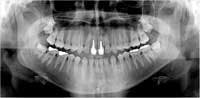

CCD-based intraoral and extra-oral digital X-ray systems can produce striking, high-resolution, diagnostic-quality digital images that rival, and in some instances, even exceed film in diagnostic quality. These solid-state-based digital radiograph systems are rapidly becoming the way of the future in the dental profession, and will no doubt soon be the adopted standard of care in our profession. (See Figures 1 and 2.)

One advantage digital images hold over film images is in the area of diagnosis and treatment-planning. A benefit that is often overlooked is the easy-to-view, large-format-size of the digital-image files when they are displayed on a CRT or LCD monitor.

Such a large image display allows for full-resolution viewing at a comfortable angle, which is conducive to a thorough and complete diagnosis. A large display provides for an easier X-ray viewing process, increases the likelihood of viewing X-rays in a more comprehensive fashion, and promotes a more thorough radiographic examination. A more thorough examination frequently will lead to increased diagnostic capabilities, both qualitatively and quantitatively. This will lead to a more complete and thoughtful treatment plan, ultimately resulting in increased treatment and the associated revenue it brings. This larger-image format is a major benefit when compared with viewing a standard No. 1- or No. 2-size film.